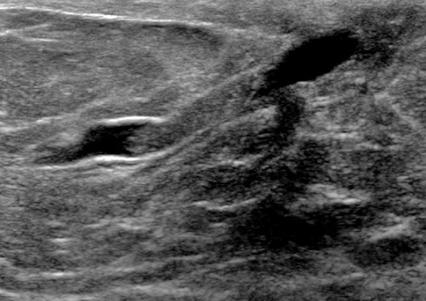

The target dataset was developed from 35 breast ultrasound scans that were segmented by an image-processing expert with extensive experience in breast lesion segmentation (the second author). The images, collected from the Web, are of different dimensions, ranging from to pixels (Figure 3, images resized for sake of illustration). These are the same images used to introduce EFIS originally [1].

Ultrasound images are generally difficult to segment, primarily due to the presence of speckle noise and low level of local contrast. It should be noted that the segmentation of ultrasound actually does require a complete processing chain, (including proper preprocessing and post-processing steps). However, the purpose of using these images was solely to demonstrate that the accuracy of the segmentation can be increased with the application of SC-EFIS.